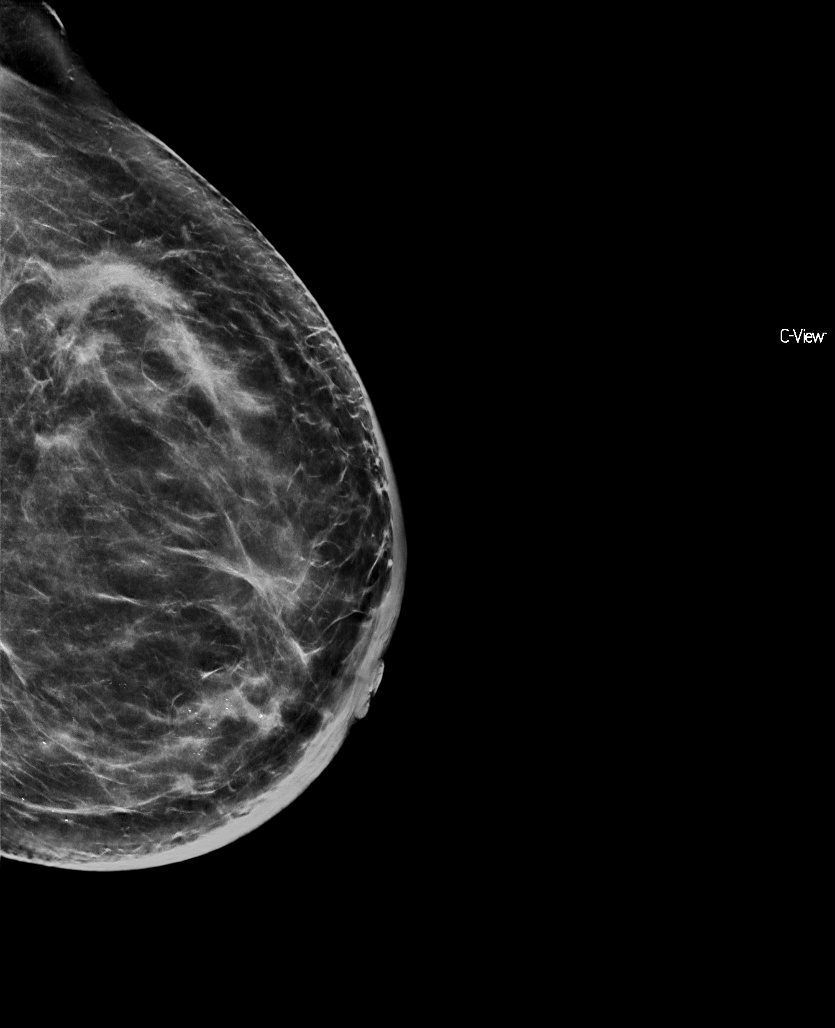

Mammography (Figure 1) and mammary ultrasound show left mammary pattern of patchy glandular type b densities, with inflammatory signs, skin thickening and some nodular lesions, being characterised as grade 4 breast-image-reporting-and-data-system (BIRADS) lesion.

Figure 1 Mammography and mammary ultrasound show a left mammary pattern of patchy glandular type b densities, with inflammatory signs, skin thickening and some nodular lesions.